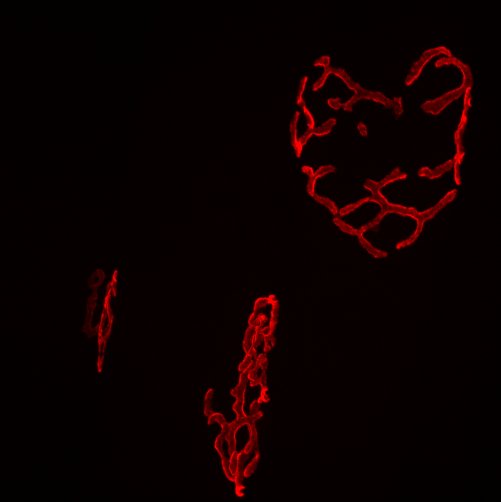

Neuromuscular junctions (NMJ) are highly specialized synapses connecting motoneuronal axons and skeletal muscles. Signal transmission at the NMJs is crucial for the functioning of the human organism. However, some of the neurodegenerative disorders affect those synapses, leading to severe consequences. The etiology of a number of those diseases is still unknown. Our laboratory studies new important regulators of NMJ with a potential to become a therapeutic target in the future. One of the candidates is cyclase-associated protein 2 (Cap2), which is known as a regulator of actin remodeling. Lack of Cap2 was already associated with severe cardiac problems in mice models and human patients. In the context of skeletal muscles, it was shown that the deletion of CAP2 leads to nemaline myopathy and hypotonia. However, it was never been studied in the context of NMJ. In my project, I'm using tissue-specific Cap2 knockouts to characterize in detail the role of Cap2 protein in neuromuscular junction development and maintenance.